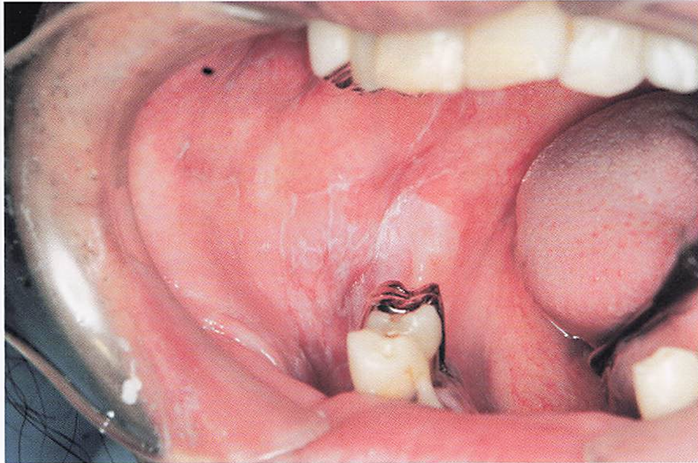

午後-49

19歳の男性。口腔内の腫脹を主訴として来院した.1週前から腫脹に気付いていたが、痛みがないため様子をみていたところ、次第に増大してきたと いう、特記すべき既往歴はない。ラヌーラと診断された。初診時の口腔内写真を別に示す。 この疾患の特徴はどれか。2つ選べ。

a.弾性軟である。

b.内部に唾液が貯留している。

c.境界不明瞭で浸潤性発育を示す。

d.胎生期に迷入した上皮に由来する。

解答を見る

a.b